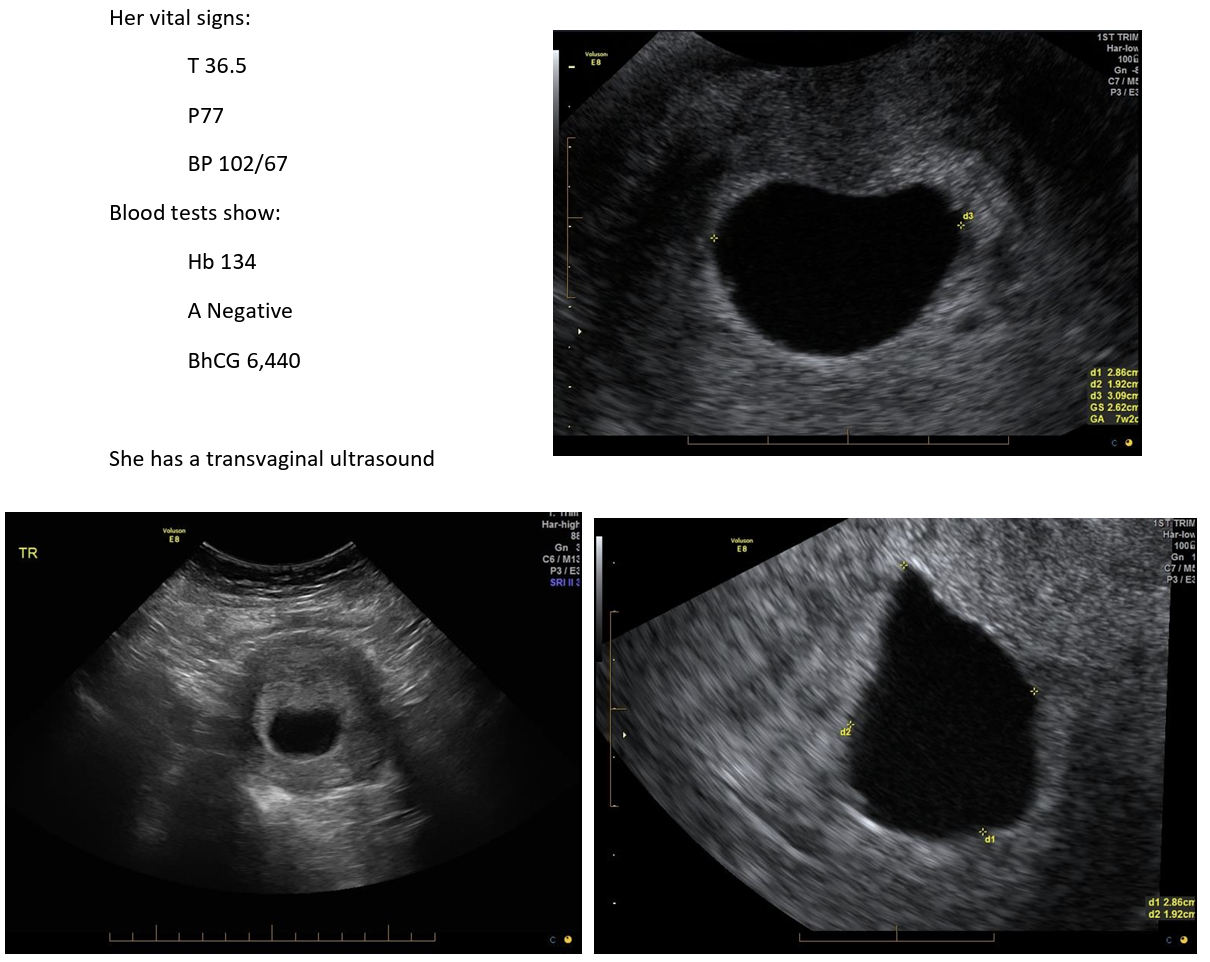

A 24 year old woman in her first pregnancy comes to the emergency department with a small amount of vaginal bleeding and lower abdominal cramping. She has no significant past medical history and has been taking folate supplementation since her positive urine pregnancy test 3 weeks ago.

Her vital signs:

T 36.5

P77

BP 102/67

Blood tests show:

Hb 134

A Negative

BhCG 6,440

She has a transvaginal ultrasound

Report states: β€œThere is an intrauterine gestational sac which has a mean sac diameter of 26.2mm but no fetal pole is visualised. There is no evidence of extrauterine pregnancy and no free fluid”

What is the diagnosis and viability of the pregnancy? (2 marks)